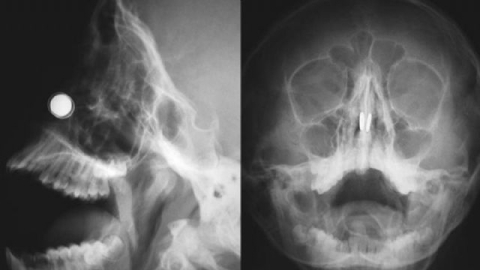

Konuyla ilgili açıklamalarda bulunan Yakın Doğu Üniversitesi Hastanesi'nde Doç. Dr. Kadir Çağdaş Kazıkdaş, en güçlü mıknatıslardan olan neodyum mıknatıslarının buruna girer girmez çocuğun burun direği etrafında birbirine yapıştığını açıkladı. Çocuğun mıknatısları burnuna soktuktan yaklaşık altı saat sonra dayanılmaz bir ağrı, burun kanaması ve burun içinde kabuklanma şikayetleri ile hastanenin acil servisine getirildiğini ifade eden Doç. Dr. Kazıkdaş, yapılan ilk müdahalede mıknatısların halen çocuğun burnunda olup olmadığının kesin olarak anlaşılamadığını, burun içerisinde de kanamaya bağlı çok fazla kabuklanma olduğunu, bu arada çocuğun duyduğu ağrı ve korku nedeniyle doktorların müdahale girişimlerini de engellediğini söyledi. Doç. Dr. Kazıkdaş daha sonra hastanın Kulak, Burun Boğaz Polikliniği'ne sevk edilerek, yüz röntgeninin çekildiğini, böylece burun içerisinde birbirine kenetlenmiş olan mıknatısların tespit edilebildiğini söyledi.

Hızlıca ameliyathaneye alınan çocuğa genel anestezi verilerek bu esnada mıknatısları çıkarmanın bir yolunun arandığını söyleyen Doç. Dr. Kadir Çağdaş Kazıkdaş; "Çocuk septal perforasyon dediğimiz, burun direğinde küçük bir delik oluşması riski altındaydı. Aynı zamanda, eğer en kısa zamanda mıknatıslar çıkarılmazsa, burun kıkırdağında kangren ya da doku ölümü gerçekleşme olasılığı da vardı" dedi.

Geleneksel cerrahi aletlerle mıknatısları çıkarmayı denediklerini ama bu şekilde sonuç alamadıklarını ifade eden Doç. Dr. Kadir Çağdaş Kazıkdaş, son olarak burun içinde kenetlenmiş olan mıknatısları kaldırıp çıkarmak için burun dışından sıradan mıknatıslar kullanmayı düşündüklerini ifade ederek şöyle devam etti; "Bu yöntem ile sol taraftaki mıknatısı kolaylıkla çıkarmayı başardık. Ardından ikinci mıknatısı çıkarmak da saniyeler sürdü. Çocuğun burun kıkırdağında oluşan hasarlı bölgeye ve travmatize olan dokulara yapay yama uygulandı. İlerleyen dönemdeki iyileşmeyi desteklemesi için silikon burun ateli de takıldı. Atel operasyon sonrasında on gün boyunca hastanın burnunda takılı kaldı."